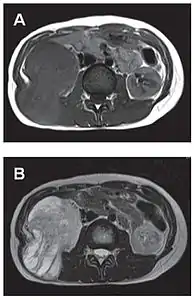

- Tumeur fibreuse solitaire du rétropéritoine

Aspect tomodensitométrique, sans (A) puis avec (B) injection de produit de contraste[44].

Aspect IRM, en séquence T1 (A) et T2 (B)[44].